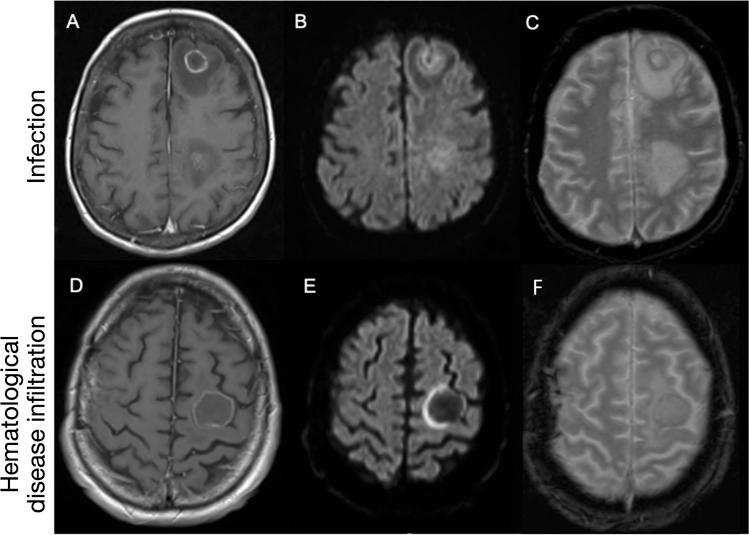

Hematological malignancies place individuals at risk of CNS involvement from their hematological disease and opportunistic intracranial infection secondary to disease-/treatment-associated immunosuppression. Differentiating CNS infection from hematological disease infiltration in these patients is valuable but often challenging. We sought to determine if statistical models might aid discrimination between these processes. Neuroradiology, clinical and laboratory data for patients with hematological malignancy at our institution between 2007 and 2017 were retrieved. MRI were deep-phenotyped across anatomical distribution, presence of pathological enhancement, diffusion restriction and hemorrhage and statistically modelled with Bayesian-directed probability networks and multivariate logistic regression. 109 patients were studied. Irrespective of a diagnosis of CNS infection or hematological disease, the commonest anatomical distributions of abnormality were multifocal-parenchymal (34.9%), focal-parenchymal (29.4%) and leptomeningeal (11.9%). Pathological enhancement was the most frequently observed abnormality (46.8%), followed by hemorrhage (22.9%) and restricted diffusion (19.3%). Logistic regression could differentiate CNS infection from hematological disease infiltration with an AUC of 0.85 where, with OR > 1 favoring CNS infection and < 1 favoring CNS hematological disease, significantly predictive imaging features were hemorrhage (OR 24.61, p = 0.02), pathological enhancement (OR 0.17, p = 0.04) and an extra-axial location (OR 0.06, p = 0.05). In conclusion, CNS infection and hematological disease are heterogeneous entities with overlapping radiological appearances but a multivariate interaction of MR imaging features may assist in distinguishing them.

血液系统恶性肿瘤使个体面临因血液系统疾病而导致中枢神经系统(CNS)受累,以及因疾病/治疗相关免疫抑制导致机会性颅内感染的风险。在这些患者中,区分中枢神经系统感染与血液系统疾病浸润具有重要意义,但通常具有挑战性。我们旨在确定统计模型是否有助于区分这些过程。检索了 2007 年至 2017 年间我院血液系统恶性肿瘤患者的神经影像学、临床和实验室数据。对 MRI 进行了深度表型分析,涉及解剖分布、病理性强化、弥散受限和出血的存在,并使用贝叶斯定向概率网络和多变量逻辑回归进行了统计学建模。共研究了 109 例患者。无论是否诊断为中枢神经系统感染或血液系统疾病,异常的最常见解剖分布为多灶性实质(34.9%)、局灶性实质(29.4%)和软脑膜(11.9%)。病理性强化是最常见的异常表现(46.8%),其次是出血(22.9%)和弥散受限(19.3%)。逻辑回归可以区分中枢神经系统感染和血液系统疾病浸润,AUC 为 0.85,其中 OR > 1 有利于中枢神经系统感染,OR < 1 有利于中枢神经系统血液系统疾病,具有显著预测价值的影像学特征为出血(OR 24.61,p = 0.02)、病理性强化(OR 0.17,p = 0.04)和外轴位置(OR 0.06,p = 0.05)。总之,中枢神经系统感染和血液系统疾病是具有重叠影像学表现的异质实体,但磁共振成像特征的多变量相互作用可能有助于区分它们。